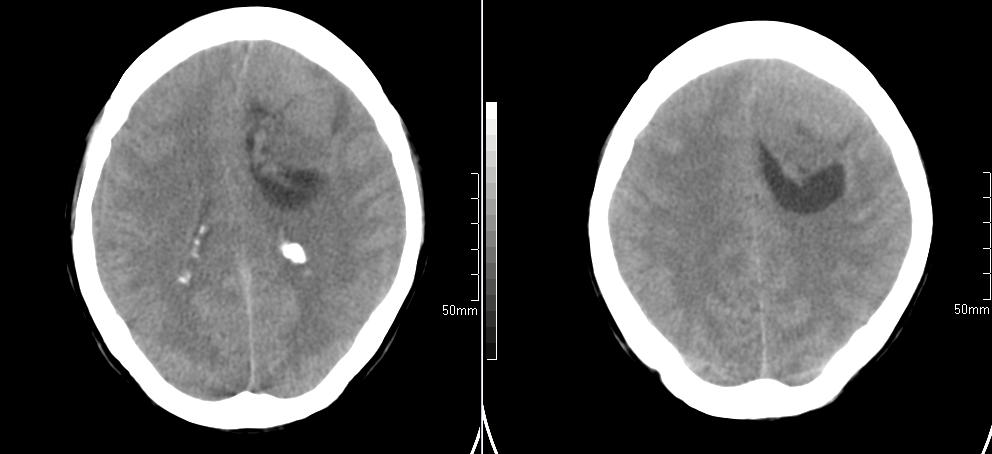

标题: CT23966:女,34岁,近一月头痛、意识障碍 [打印本页]

标题: CT23966:女,34岁,近一月头痛、意识障碍

左侧额叶见不规则软组织影,部分囊变,病变略呈等密度,占位效应明显,考虑血母可能。脑膜瘤不除外

左侧额叶肿瘤样病变,成等密度,其内可见囊变,肿瘤似与大脑镰相连,周围水肿不明显。考虑脑膜瘤可能!建议强化或mri。

左额叶囊实性肿块,实性部分呈等密度,密度不均,考虑胶质瘤可能性大,脑膜瘤及室管膜瘤不除外,建议mri增强扫描。

左额叶较大等低混杂密度影,占位效应明显,首先考虑:左额叶胶质瘤。